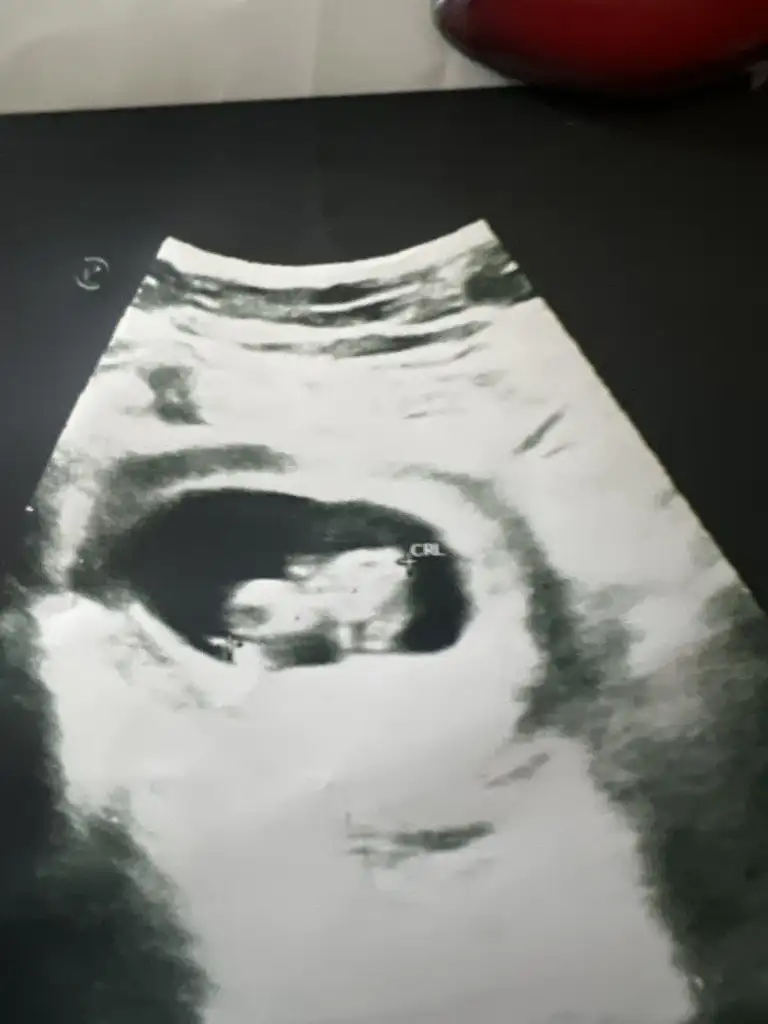

6-9 Haftalardaki ultrason görüntüsü varsa gönder beni etiketle yorumlıyım canım burda büyük ben bu şekilde anlamıyorumBanada 12 de erkek 16 da kız dedi anlayan varmı ultrasondan

Vajinelse kız karındansa erkekEki Görüntüle 3209108 7 haftalık teşekkür ederim

6-9 Haftalık ultrason görüntüsü yollarsanız bakayım böyle bilemiyorum maalesef nub anlamıyorumMerhaba banada bir tahminde bulunabilirmisiniz. Teşekkürler 15 haftalık Eki Görüntüle 3208672

Merhaba 6-8 haftalık fotosu var mı burda plesanta tam anlaşılmıyordaBenimkine de bakar mısınız

6-8 haftalık ultrason fotosu varsa atın yorumlayayım burda bebek büyük, plesanta anlaşılmıyor10 haftalık bizede bakabilirmisinizEki Görüntüle 3210511